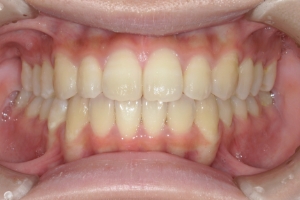

BEFORE

治療前

PROCESS

半年

AFTER

治療後

下の前歯が上あごの歯ぐきに当たるほど噛み合わせが深く、そのことが原因で上顎歯列の正中にすき間(正中離開)が生じていました。部分矯正ですき間を無理やり閉じても、噛み合わせが深いままでは治療後の再発リスクが高くなります。そのため全体矯正で奥歯の噛み合わせを整え、噛み合わせを浅くしつつ前歯を並べました。正中離開は戻りやすい傾向があるので、再発を防ぐため固定式リテーナーを推奨しています。